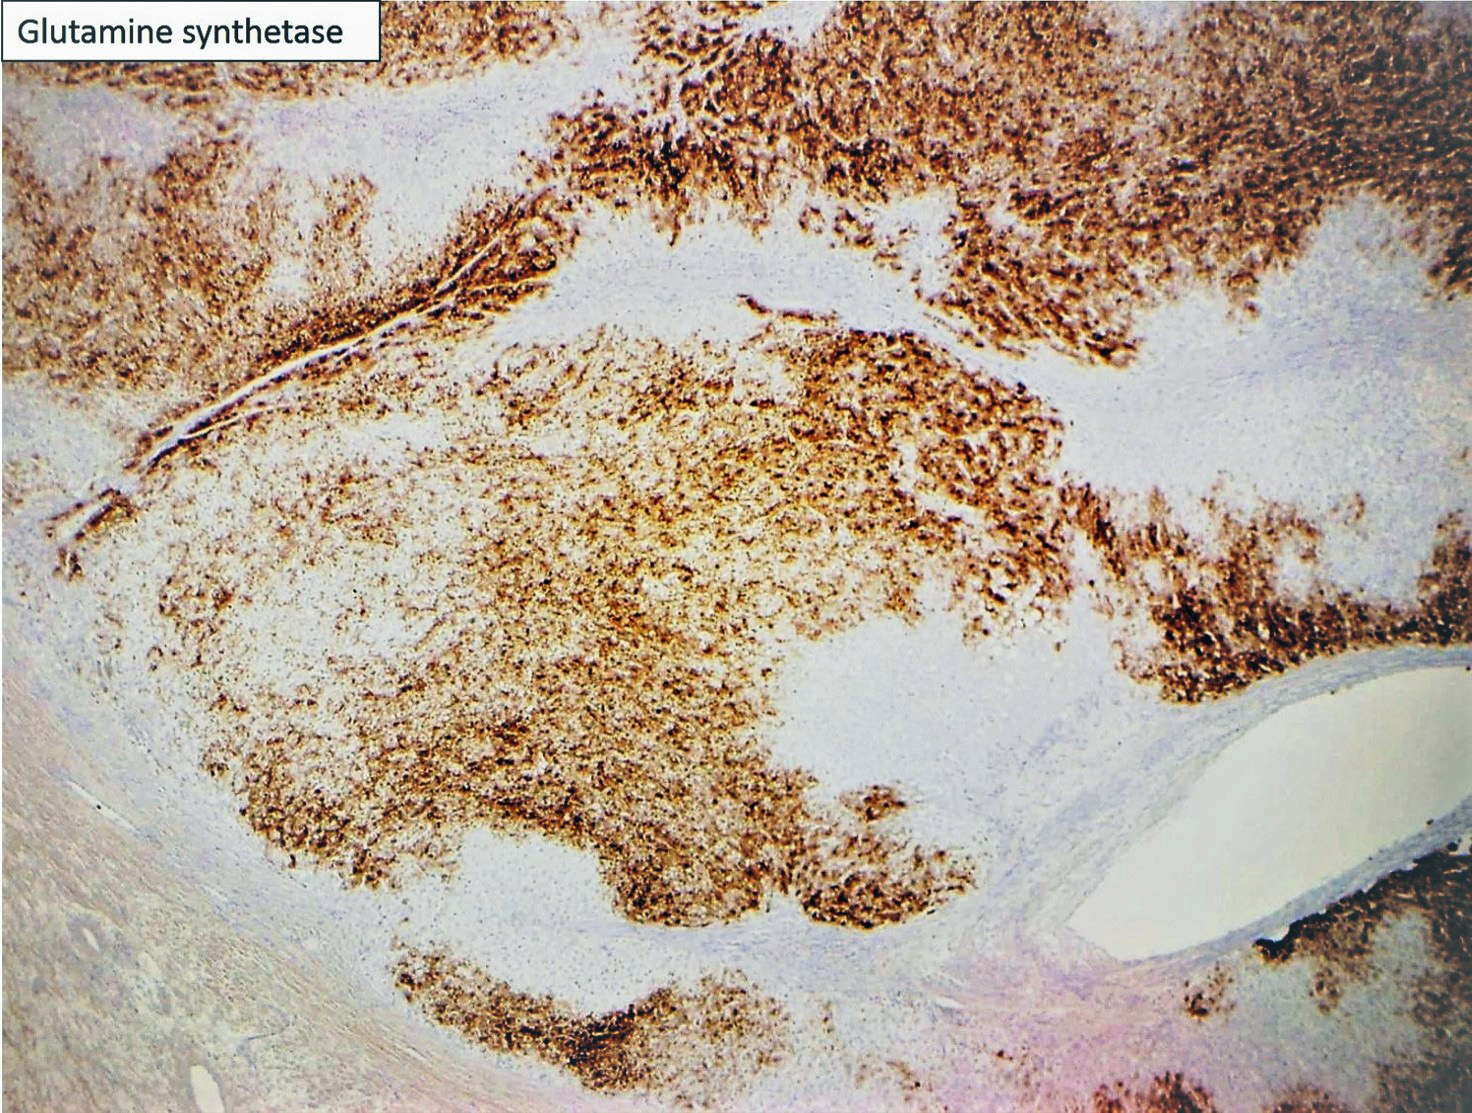

Focal nodular hyperplasia (FNH) is reactive lesion that is composed of hepatocytes and bands of fibrosis that occur due to vascular shunting in noncirrhotic liver. Usually FNH is a single lesion that most often seen in young and middle-aged women. Macroscopically, it is well-demarcated tan sub capsular mass with central stellate scar. Histologically, on low magnifications, it resembles cirrhosis with nodularity and band of fibrosis. The hepatocytes lack cytologic atypia. Multifocal areas of bile ductular proliferation (metaplasia) often seen at the interface of the hepatic parenchyma and the fibrous bands. Abnormal thick walled arteries are present in the center of the fibrous bands. Glutamine synthetase immunohistochemical stain shows an irregular blotchy/patchy pattern “maplikepattern”. While it has diffuse staining pattern in both hepatic adenomas (Beta catenin mutated) and HCC. The lesional cell show shows low proliferation index by Ki 67 immunohistochemical stain (<1%). Glypican-3 immunostain is negative. Reticulin special stain demonstrates normal reticulin pattern. It was hypothesized that FNH might be a precursor to FLC. However, there has been no proof until now to support this idea. The FNH that surrounds a small subset of FLC considers as a reaction to the tumor itself and not a precursor. [6]

Hepatic adenomas (except the androgen related subtype) and FNH do not have cytologic atypia or mitosis. They both usually occur in young middle-aged women. While FNH do not has malignant potential, 10% of the hepatic adenoma reported to in the literature have underwent malignant transformation. Inflammatory/ telangiectatic adenoma might be somehow a challenge to differentiate from FNH (especially on biopsy). The bile ductular proliferation in the inflammatory/telangiectatic hepatic adenoma is typically patchy and located in faux portal tracts and not fibrous bands. They typically have dilated (telangiectatic) and congested sinusoids, with large aberrant arteries in the parenchyma. They might have inflammation (but not seen in all cases). This type of adenoma is positive for serum amyloid A (which is negative in the normal liver). Some cases might also be Beta Catenin nuclear positivity; which then will be called Inflammatory/telangiectatic hepatic adenoma with Beta catenin activation. Glutamine synthetase is negative in the inflammatory/telangiectatic type, while it shows map like pattern in FNH. It could be positive in Beta catenin mutated type.